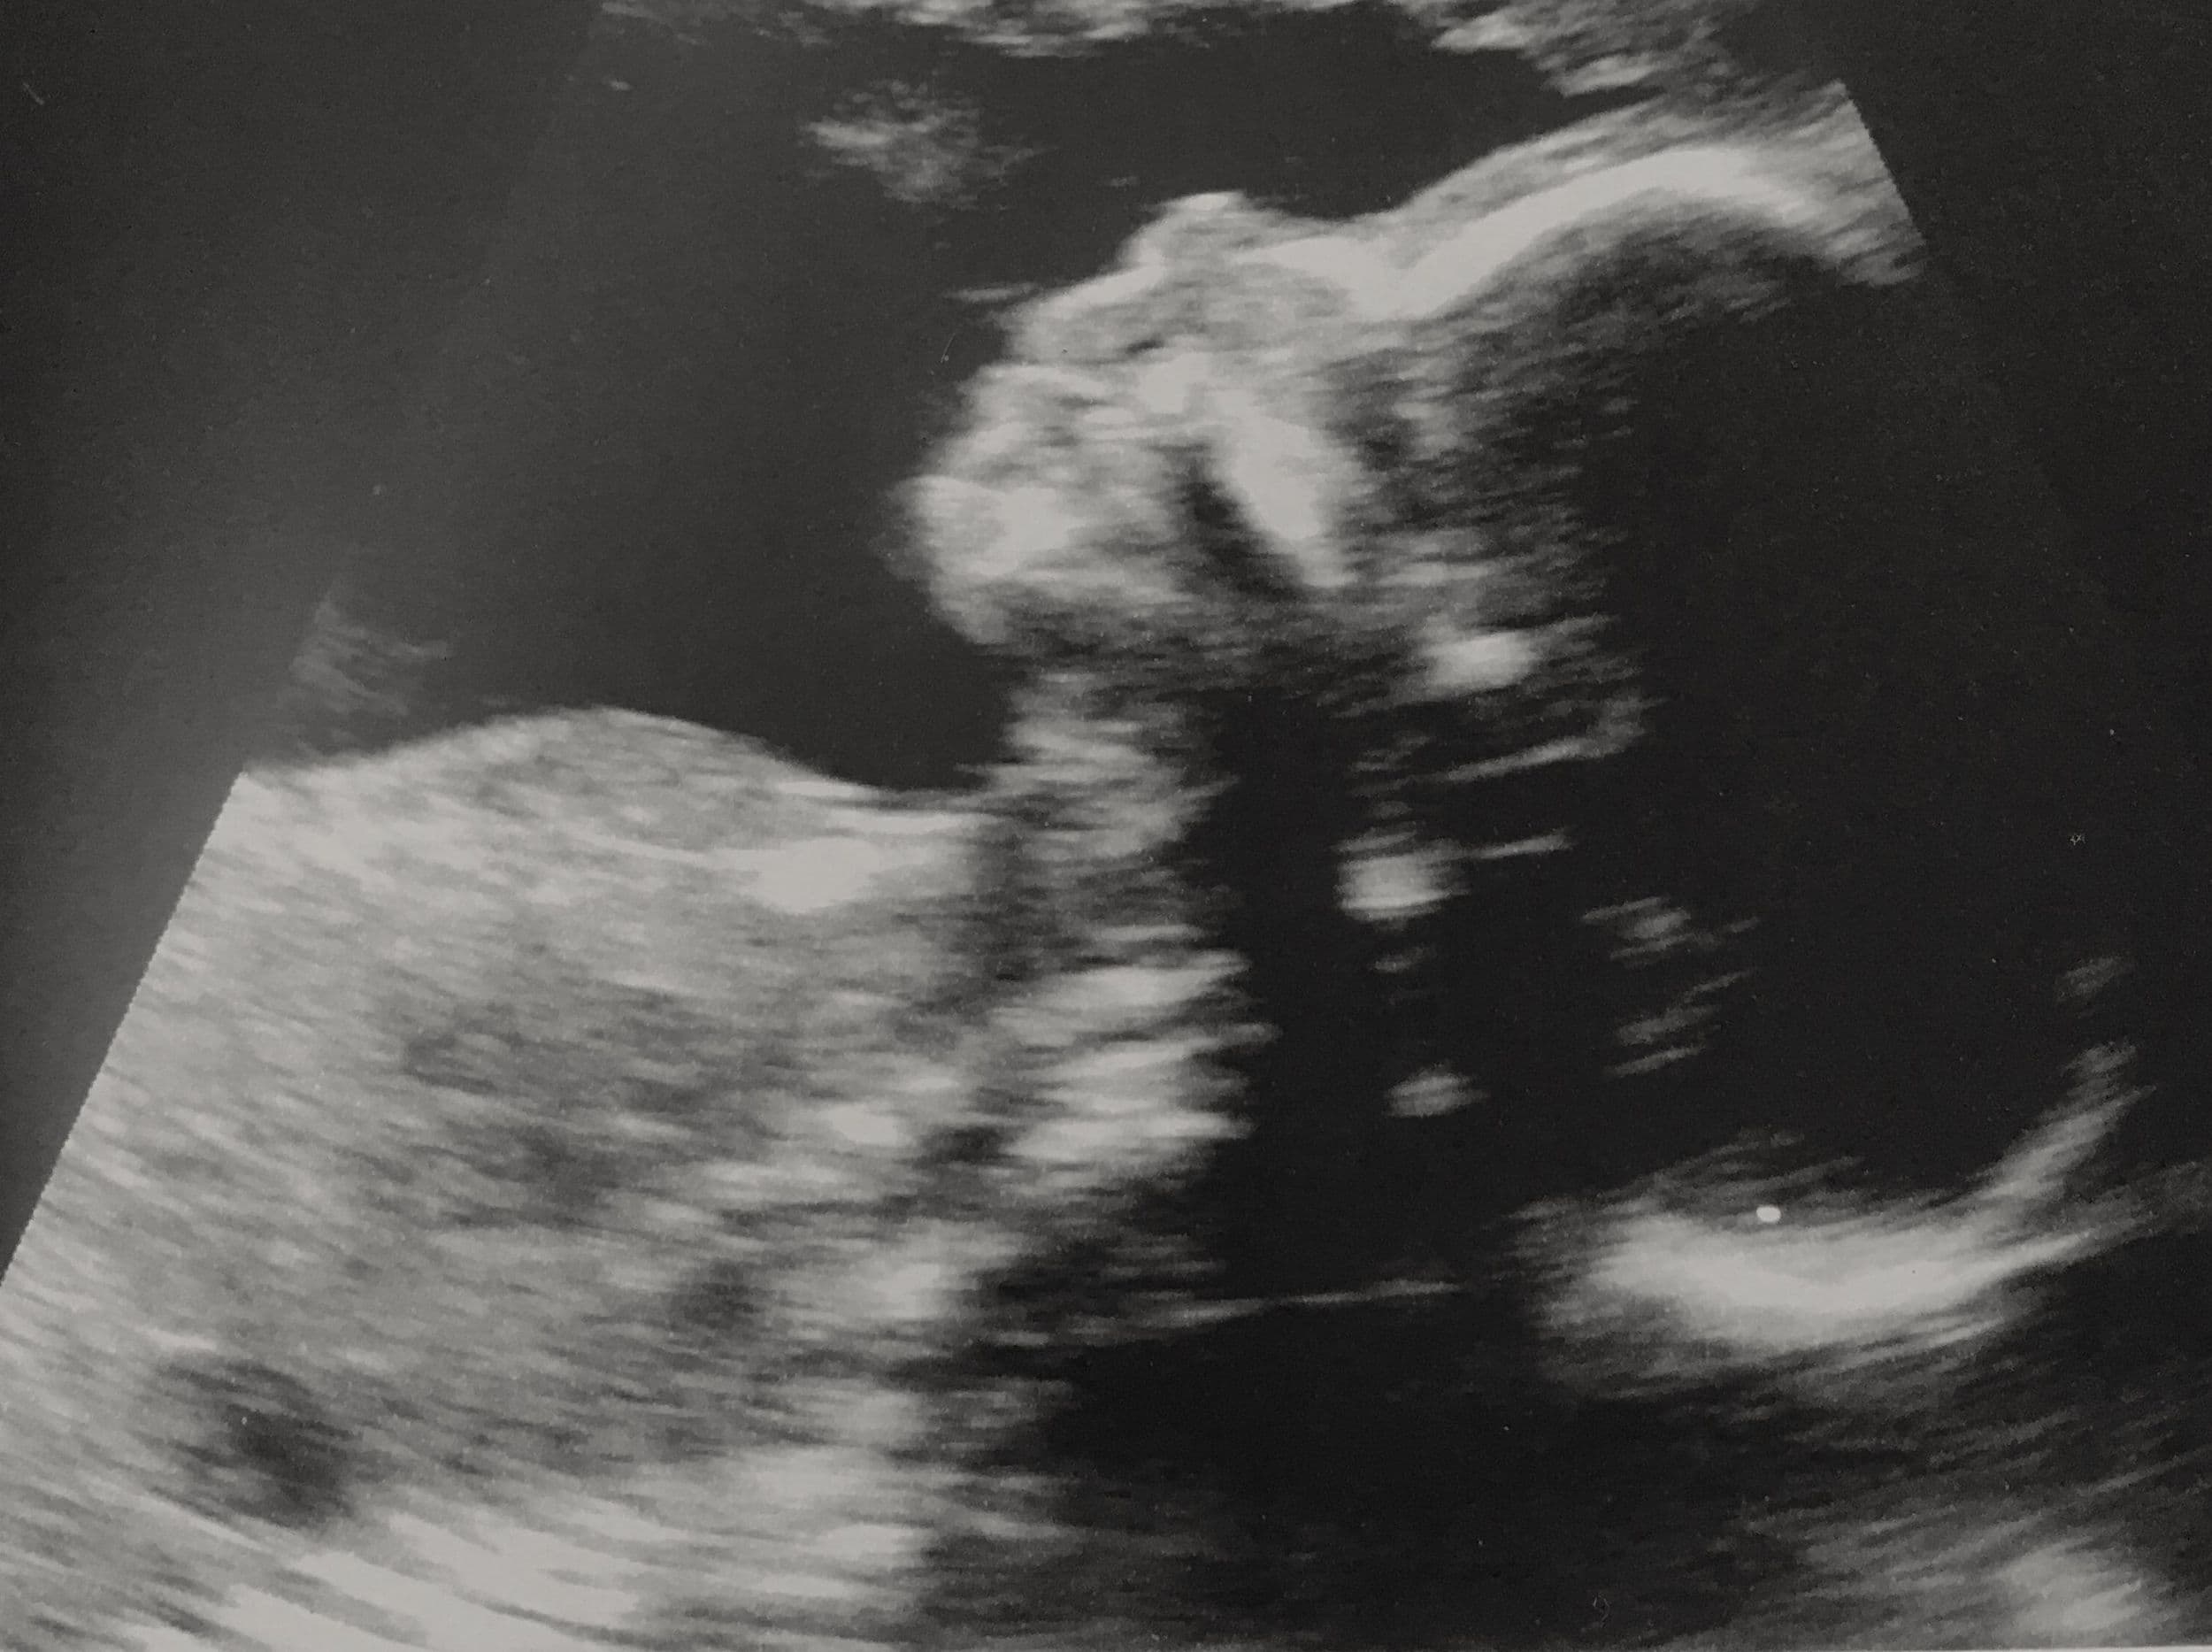

When the pregnancy hits the 20th week of gestation, an anatomy ultrasound is often ordered. This sonogram is used to determine fetal anomalies, the baby's size and weight, and also to measure growth to ensure that the fetus is developing properly.

Many ultrasound technicians will print off various pictures of the face (and occasionally the sex organs) for mom and dad to enjoy. These pictures will vary based upon whether the scan completed is a 2D, 3D or 4D scan. More advanced ultrasounds can render a 3 dimensional picture of baby for mom and dad to enjoy.